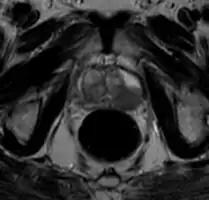

Ultrasound and magnetic resonance imaging (MRI) are the two main imaging methods used for prostate cancer detection.

MRI Organ-confined prostate cancer

MRI

On MRI, the central and transitional zones both have lower T2 signal than the peripheral zone. Since the central and transitional zones cannot be distinguished from each other, they can be best described as the central gland on MRI. Thus, the peripheral gland has a higher signal on T2WI than the central gland. In the peripheral gland, prostate cancer appears as a low-intensity lesion. However, in the central gland, low-intensity lesions cannot be distinguished from the low-intensity central gland. Diffusion restriction is instrumental in identifying and characterizing central gland lesions. Lymphadenopathy can be seen best on postcontrast, fat-suppressed T1WI.

Other regions can be described on MRI. The anterior fibromuscular stroma and the prostate capsule along the posterior and lateral prostate have a low T2WI signal, in contrast with the bright signal of the peripheral zone. Extraprostatic extension can be seen with disruption of capsule integrity.